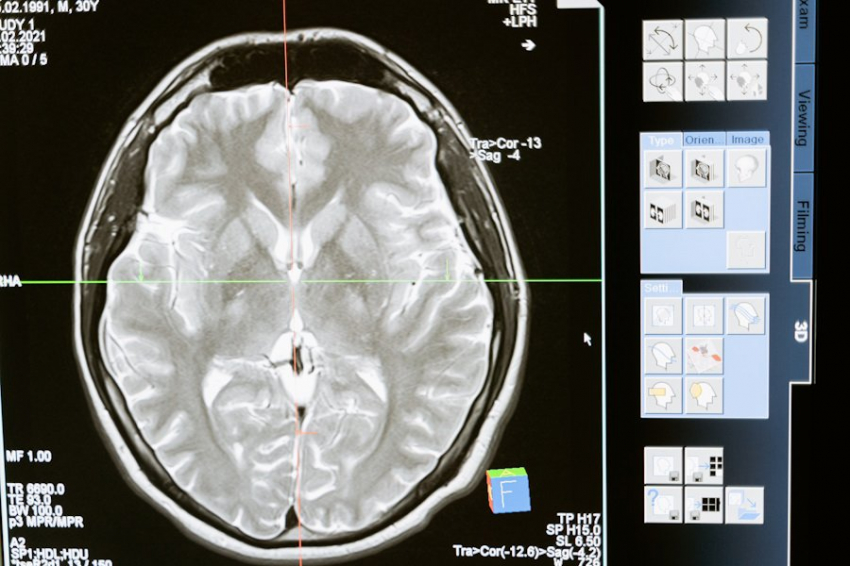

Исследование специалистов из Эдинбургского университета привело их к выводу о неожиданном источнике неврологических патологий. Провокаторами оказались микроорганизмы, населяющие головной мозг. Об открытии рассказало издание LiveScience (LiveSci).

Еще в 2013 году впервые была озвучена гипотеза о том, что мозг человека имеет собственный микробиом. Раньше считалось, что этот орган остается стерильным, туда из крови не попадают бактерии и иные вредные агенты.

Здоровый мозг защищен так называемым гематоэнцефалическим барьером. Это физиологический барьер между кровеносной и центральной нервной системой, выполняющий роль естественного фильтра. Но при старении и ряде неврологических заболеваний, таких как болезнь Альцгеймера, данная функция частично утрачивается. И патогены могут проникать в мозг.

Исследователями из Эдинбургского университета доказано, что в мозге людей с болезнью Альцгеймера наблюдается больше разнообразия бактерий и грибков, чем у здоровых людей. Но как именно нарушается микробиом мозга, пока в точности не известно.